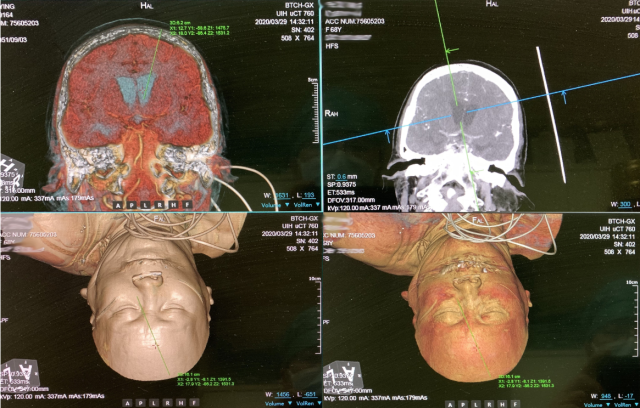

图为北京清华长庚医院三维CT重建,模拟手术穿刺路线